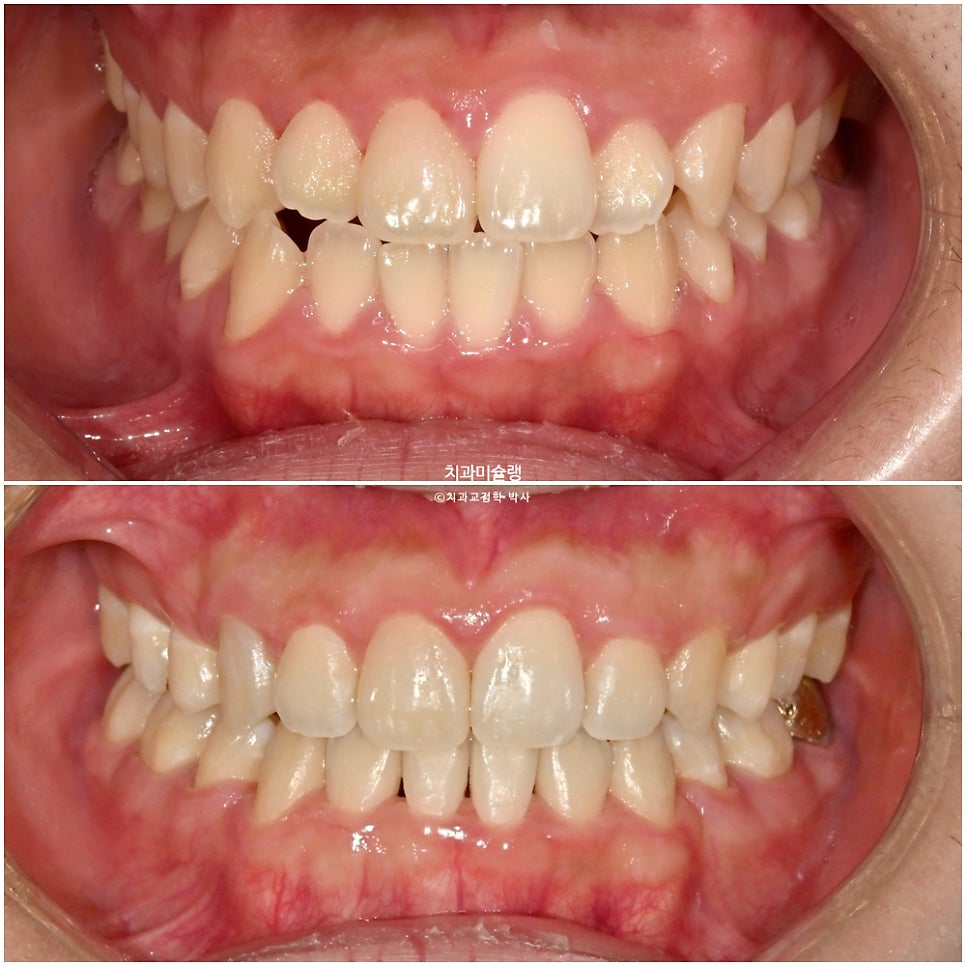

초진 시 구강 상태

중심선 불일치, 반대교합, 덧니 등이 보입니다.

앞니가 뻗친 돌출 입니다.

입이 잘 안다물어질 정도의 돌출입이며 웃을때 잇몸이 과하게 보이는 거미스마일도 있습니다.

2026년 2월 치료 완료

중심선은 정확히 맞으며 앞니 교합은 좋습니다.

어금니 교합은 물샐틈 없는 1급 교합관계를 보입니다.

치료 결과 비교

이제 전후 비교 볼게요.

웃을때의 잇몸 노출량은 상당히 줄었으며 편평한 아랫입술에 비하면 스마일라인도 적절한 편입니다.

앞니 뻗침이 개선되어 깔끔한 미소

돌출입은 잘 해결되었습니다.